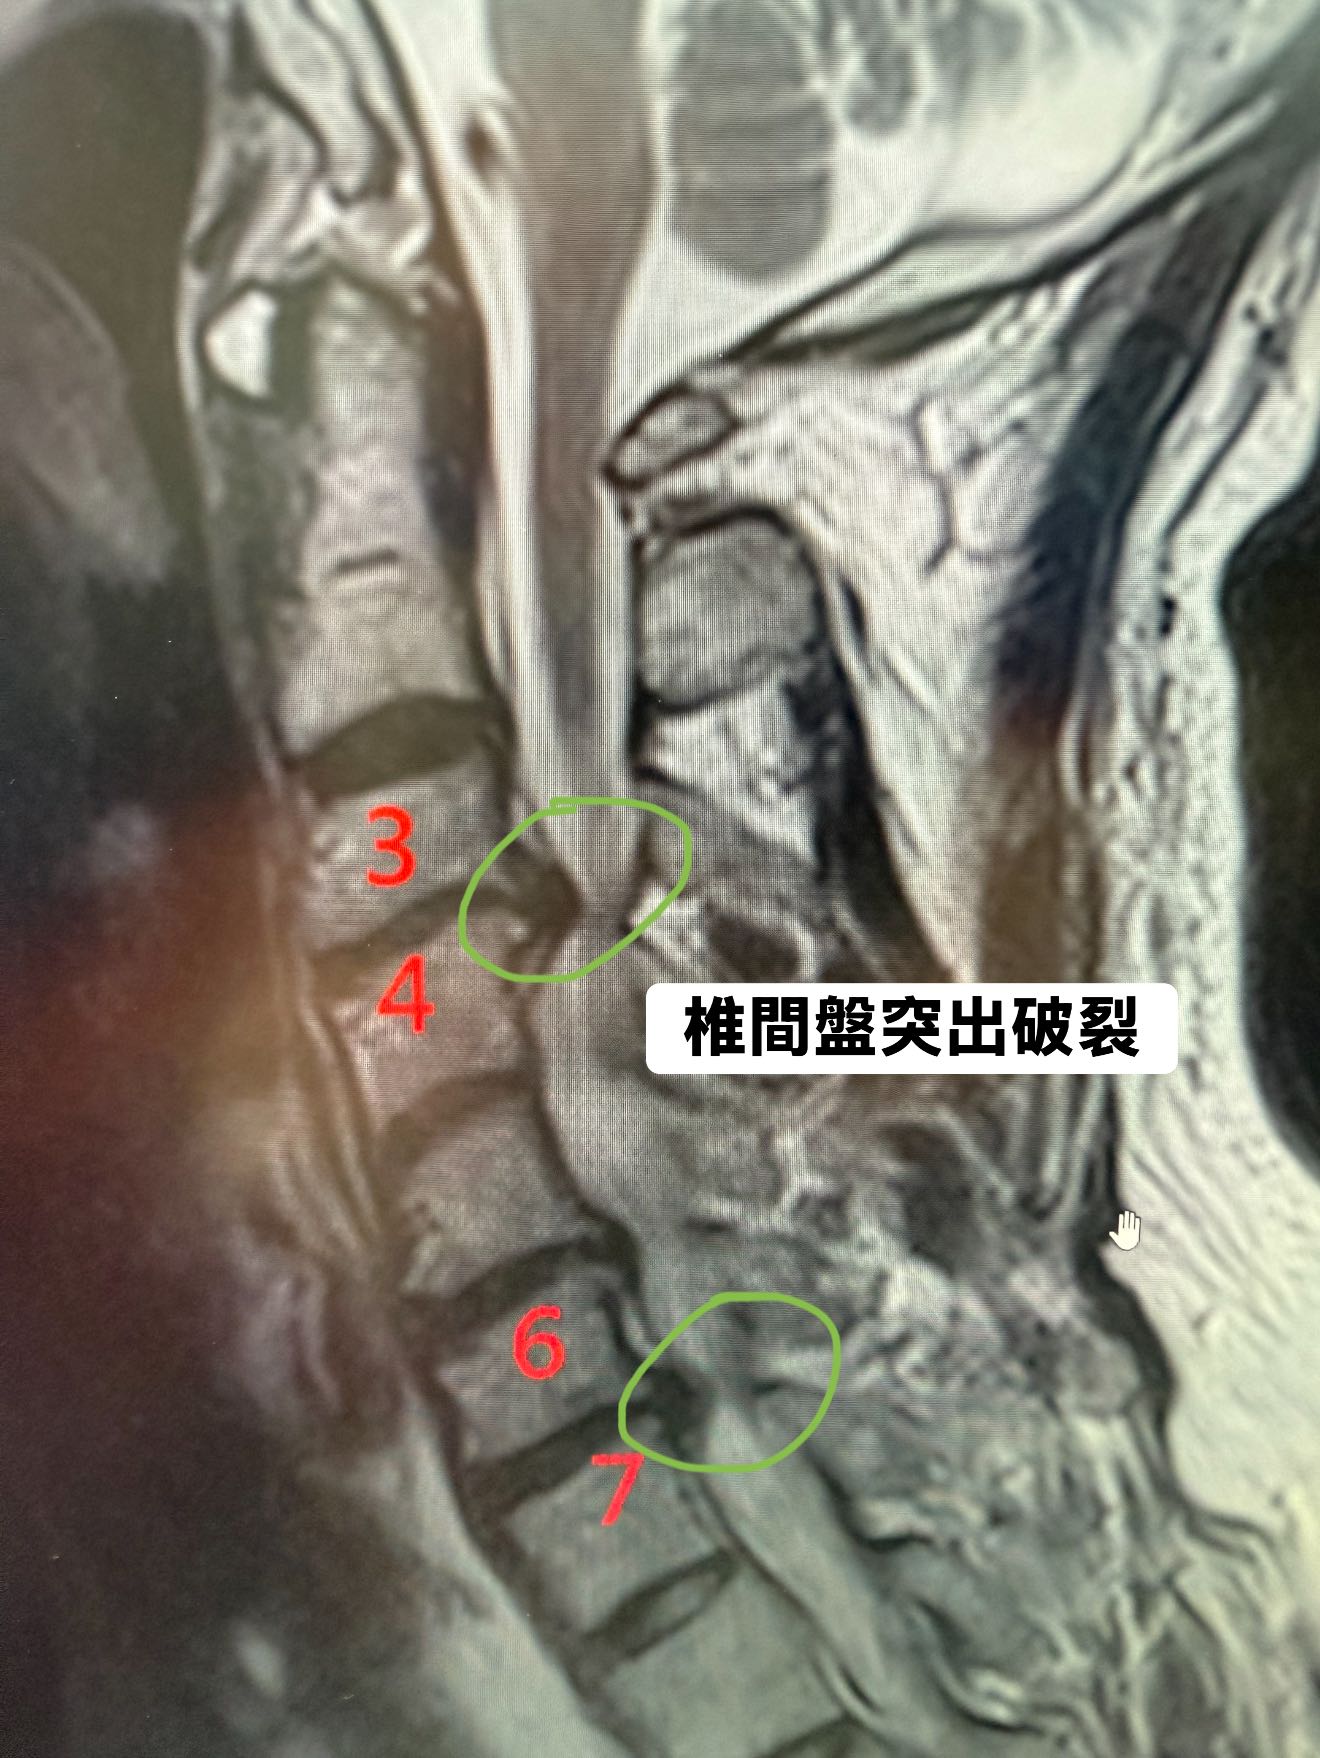

Cervical Spine Treatment Cases 頸椎治療案例 標題:當香港跟倫敦所有名醫都說頸椎必須開大刀:一位香港母親,如何在台北三週內逆轉... 2026.03.18 「徐國峰醫師的診間針刀筆記」 影像上的「死刑」,針尖下的「新生」:一個跨越 2500 ... 2026.03.03 飛鷹歸來:解開 9G 鎖喉的「脊椎減壓」奇蹟 —— F-16 飛官龔先生頸椎減壓針刀復原長... 2026.01.15 醫案深探:當頸椎失去靈魂的曲線,神經根在狹縫中求生。 深夜的痛覺,為什麼你的頸椎... 2026.01.11 「不是花粉!不是塵蟎!長年過敏性鼻炎的真正原因,可能藏在你的頸椎深層筋膜裡」 文... 2025.12.08 🌟新竹范小姐的頸椎奇蹟醫案分享 ——手術與非手術之間,她找到屬於自己的第三條路 ✅... 2025.12.03 脊椎噩夢兩年三開!花費新台幣三百萬元 頸椎手術黑洞蒸發公務員積蓄:300萬,換不回... 2025.11.21 ⭕️低頭的代價:智慧手機正在悄悄「鎖死」台灣八百萬長輩們的殘破頸椎 🛑頸椎人工椎間... 2025.11.06 跨越半個地球的希望:華僑黃阿姨的頸椎奇蹟。 美國頸椎手術ACDF要價台幣150-250萬。 ... 2025.10.03 【200公斤水泥的血淚啟示:揭開你頸椎上「慢性重量」的驚人真相與致命代價! 【⚠️ 醫... 2025.09.29 ❇️頸椎推拿的風險警鐘:從一個真實案例談起 ‼️電流竄過手臂的那一瞬間,他的人生被改... 【醫療案例探討真相|PRP打進頸椎椎間盤?一名患者一年的手腳無力,背後的風險不可不... 2025.08.16 🚨 MRI 一張 → 馬上開刀?自費五十多萬更換兩節人工椎?廚師的抉擇 (文:徐國峰醫師... 2025.08.13 【當針刀無法再沉默——一位針刀醫師關於「非手術底線」的誠實告白】 【不是每一個人... 一張86萬的頸椎手術帳單,讓我們重新認識什麼叫做「選擇」。 「問題關鍵不是價格,而... 1 2 3 4 5 下一頁 →